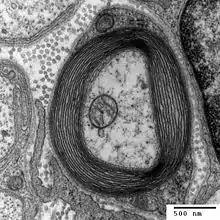

Il découvre dans les fibres du système nerveux périphérique, des cellules, appelées aujourd'hui cellules de Schwann, recouvertes d'une couche protectrice, constituant ce qu'on appelle aujourd'hui la gaine de Schwann.